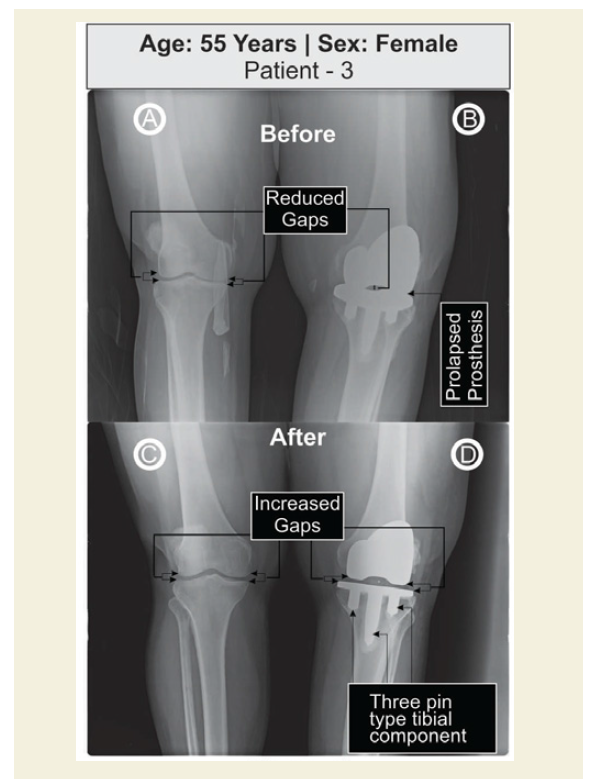

Four female patients aged 65, 73, 55 and 64 years old respectively advised to further revision of unilateral TKR because they suffered with severe pain on weight-bearing, impaired function, and limitations of daily activities. They were treated at OPTM Healthcare (P) Ltd., India, from January 2016 to July 2016. The study protocol was evaluated and approved by the OPTM Research Institute Ethics Committee. An institutional review board-approved consent form for physical examinations and bilateral knee-joint images (X-rays) required for the study was signed by all four patients. Baseline demographic characteristics of four patients are shown in Table 1. The said four patients were not being treated by oral medications; injections; massage with any type of herbal gels; and any type of alternative interventions or treatments for diminishing pain or inflammation, for muscle relaxation, or to improve of the skeletal muscles during the last four weeks prior to the treatment of 90 days. The radiological features were observed bone erosion and revision for further prosthesis needed in the post-operated knee joint and required surgical intervention in the non-surgical knee joint as the patients were suffering with severe pain, stiffness and physical functional disabilities in both the kneejoints (Table 1) (Figures 1A,1B,2A,2B,3A,3B,4A and 4B). Four pair of radiological images (before and after) is depicted in Figures 1-4.

Tables 2 and 3, summarize the pain and performance parameters of four patients. Patients underwent standing X-ray examination to the most important leg joints and lower back: it confirmed knee involvement with large osteophytes, narrowing the joint space, increased density of the subchondral bone, large subchondral cysts in the non-operated knee joints. The joint spaces of the operated knee joint were completely jointed in case of patients 1 and 3, substantially diminished in case of patient 2 and stucking the long fixed pin at the highcorner of the femoral compartment in case of patient 4 (Figures 1-4).

After 90 days of topical phytotherapeutic treatment, improvements were observed in pain under visual analogue scale (VAS) and pain, stiffness and physical function under WOMAC Index with highly significant values (p<0.05); improvements of functional performance under the Karnofsky performance scale (KPS) and reduction of obesity as confirmed by body mass index (BMI) were also highly statistically significant (p<0.05) (Table 3) (Figures 5 and 6). A substantial improvement of the knee-joints (both non-operated and operated) have also been observed as evidenced by X-ray imaging (Figures 1C,1D,2C,2D,3C,3D,4C and 4D).

The present case reports indicate the failure in TKR and osteoporosis after TKR with pain and non-performance of daily activities for which alternative treatment with specialised topical phytotherapy for 90 days would be considered to be best. Generally, the TKR supports to relief pain and improvement of performance in daily activities [1,2]. Further revision on TKR may be stressful, risk and expensive but specialized topical phytotherapeutic treatment after 90 days to the studied patients are suitable therapy where substantial improvement in pain, stiffness, functional and performance abilities, BMI with highly statistically significant values (p<0.05), knee gaps, osteoporosis and osteophytes in non-operated knee-joint and knee flexion were observed (Table 3) (Figures 1C,1D,2C,2D,3C,3D,4C,4D,5 and 6).

The aim of the TKR is to reduce the pain, increase the functional ability and the gap between the femoral and tibial compartments. The present study firmly confirmed with normalization of prolapsed prostheses by increasing the gap between the compartments of the operated and non-operated knee-joints as evidenced by X-ray images and diminishing pain, stiffness and improvement of physical functional and performance abilities and reduction of inflammation as well as obesity confirmed by BMI with the help of topical phytotherapeutic method within 90 days (Table 3) (Figures 1C,1D,2C,2D,3C,3D,4C,4D,5 and 6).